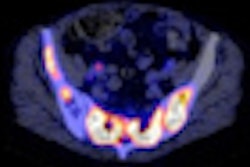

The value of quantitative analysis of F-18 FDG PET images in oncology, using parameters such as standardized uptake value (SUV), is increasingly of interest. Such parameters are potential indicators of prognosis early on in a patient's treatment course. However, variation in photon attenuation with tissue depth and the blurring effects of breathing motion introduce inaccuracies that must be corrected for if such information is to be exploited fully (Phys Med Biol, January 21, 2012, Vol. 57:2, pp. 309-328).

CT-based attenuation correction and respiratory gating are popular solutions to resolve these problems. Respiratory-gated CT is phase-matched to correct for attenuation in gated PET data, which in turn is used to separate photons from different respiratory phases. However, this process involves extended, continuous CT data acquisition over several breathing cycles, which can result in effective doses to the patient as high as 16 mSv.

Furthermore, sinogram smoothing was found to reduce CT noise in ultralow-dose scans, enhancing the capacity of the CT data to correct for attenuation in accompanying PET data. Indirectly, this strategy was demonstrated to reduce CT dose by up to a factor of three. The combined effects of these methods indicated the effective dose from the CT component of the PET/CT scan could be reduced from 16 mSv to less than 3 mSv without degrading PET image quality.